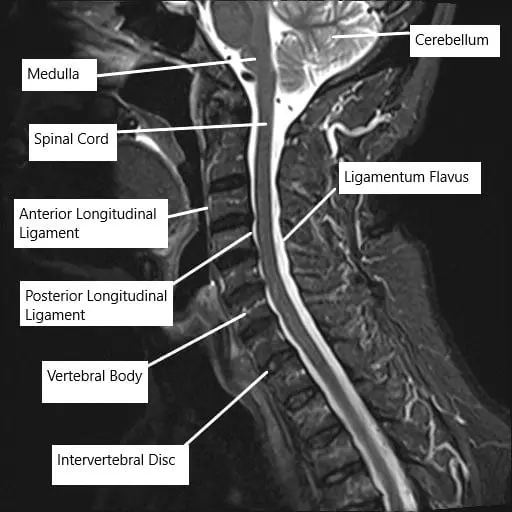

MRI of the cervical spine showing the various ligaments surrounding the spinal cord.

The posterior longitudinal ligament runs along the back surface of the vertebral bodies inside the spinal canal. Its job is to stabilize the spine and limit excessive movement. When the ligament thickens and hardens, it takes up space in the canal, squeezing the spinal cord. This pressure can interrupt signals between the brain and body, leading to numbness, weakness, or coordination problems.